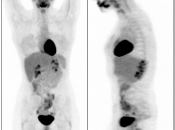

Normal Skeletal Uptake

Mild to moderate FDG uptake can be normally seen within red marrow, most commonly affecting the vertebral bodies, sternum, pelvis, and proximal long bones (it is not unusual to see fairly prominent uptake within the proximal half of the femurs). This red marrow uptake can be quite heterogeneous at times, yet still normal.

Diffuse Skeletal Uptake:

Intense and diffuse reactive marrow uptake is frequently seen as the result of chemotherapy and/or colony stimulating factors (discussed in detail, here).

If rather diffuse and intense uptake is noted without a history of recent chemotherapy or colony stimulating factors, be suspicious of infiltrating disease such as lymphoma.

Focal Skeletal Uptake:

Focal skeletal uptake warrants extremely close assessment of the co-registered CT images to exclude malignancy. Other etiologies of focal skeletal uptake include fracture, arthropathy, infection and several benign bone lesions.